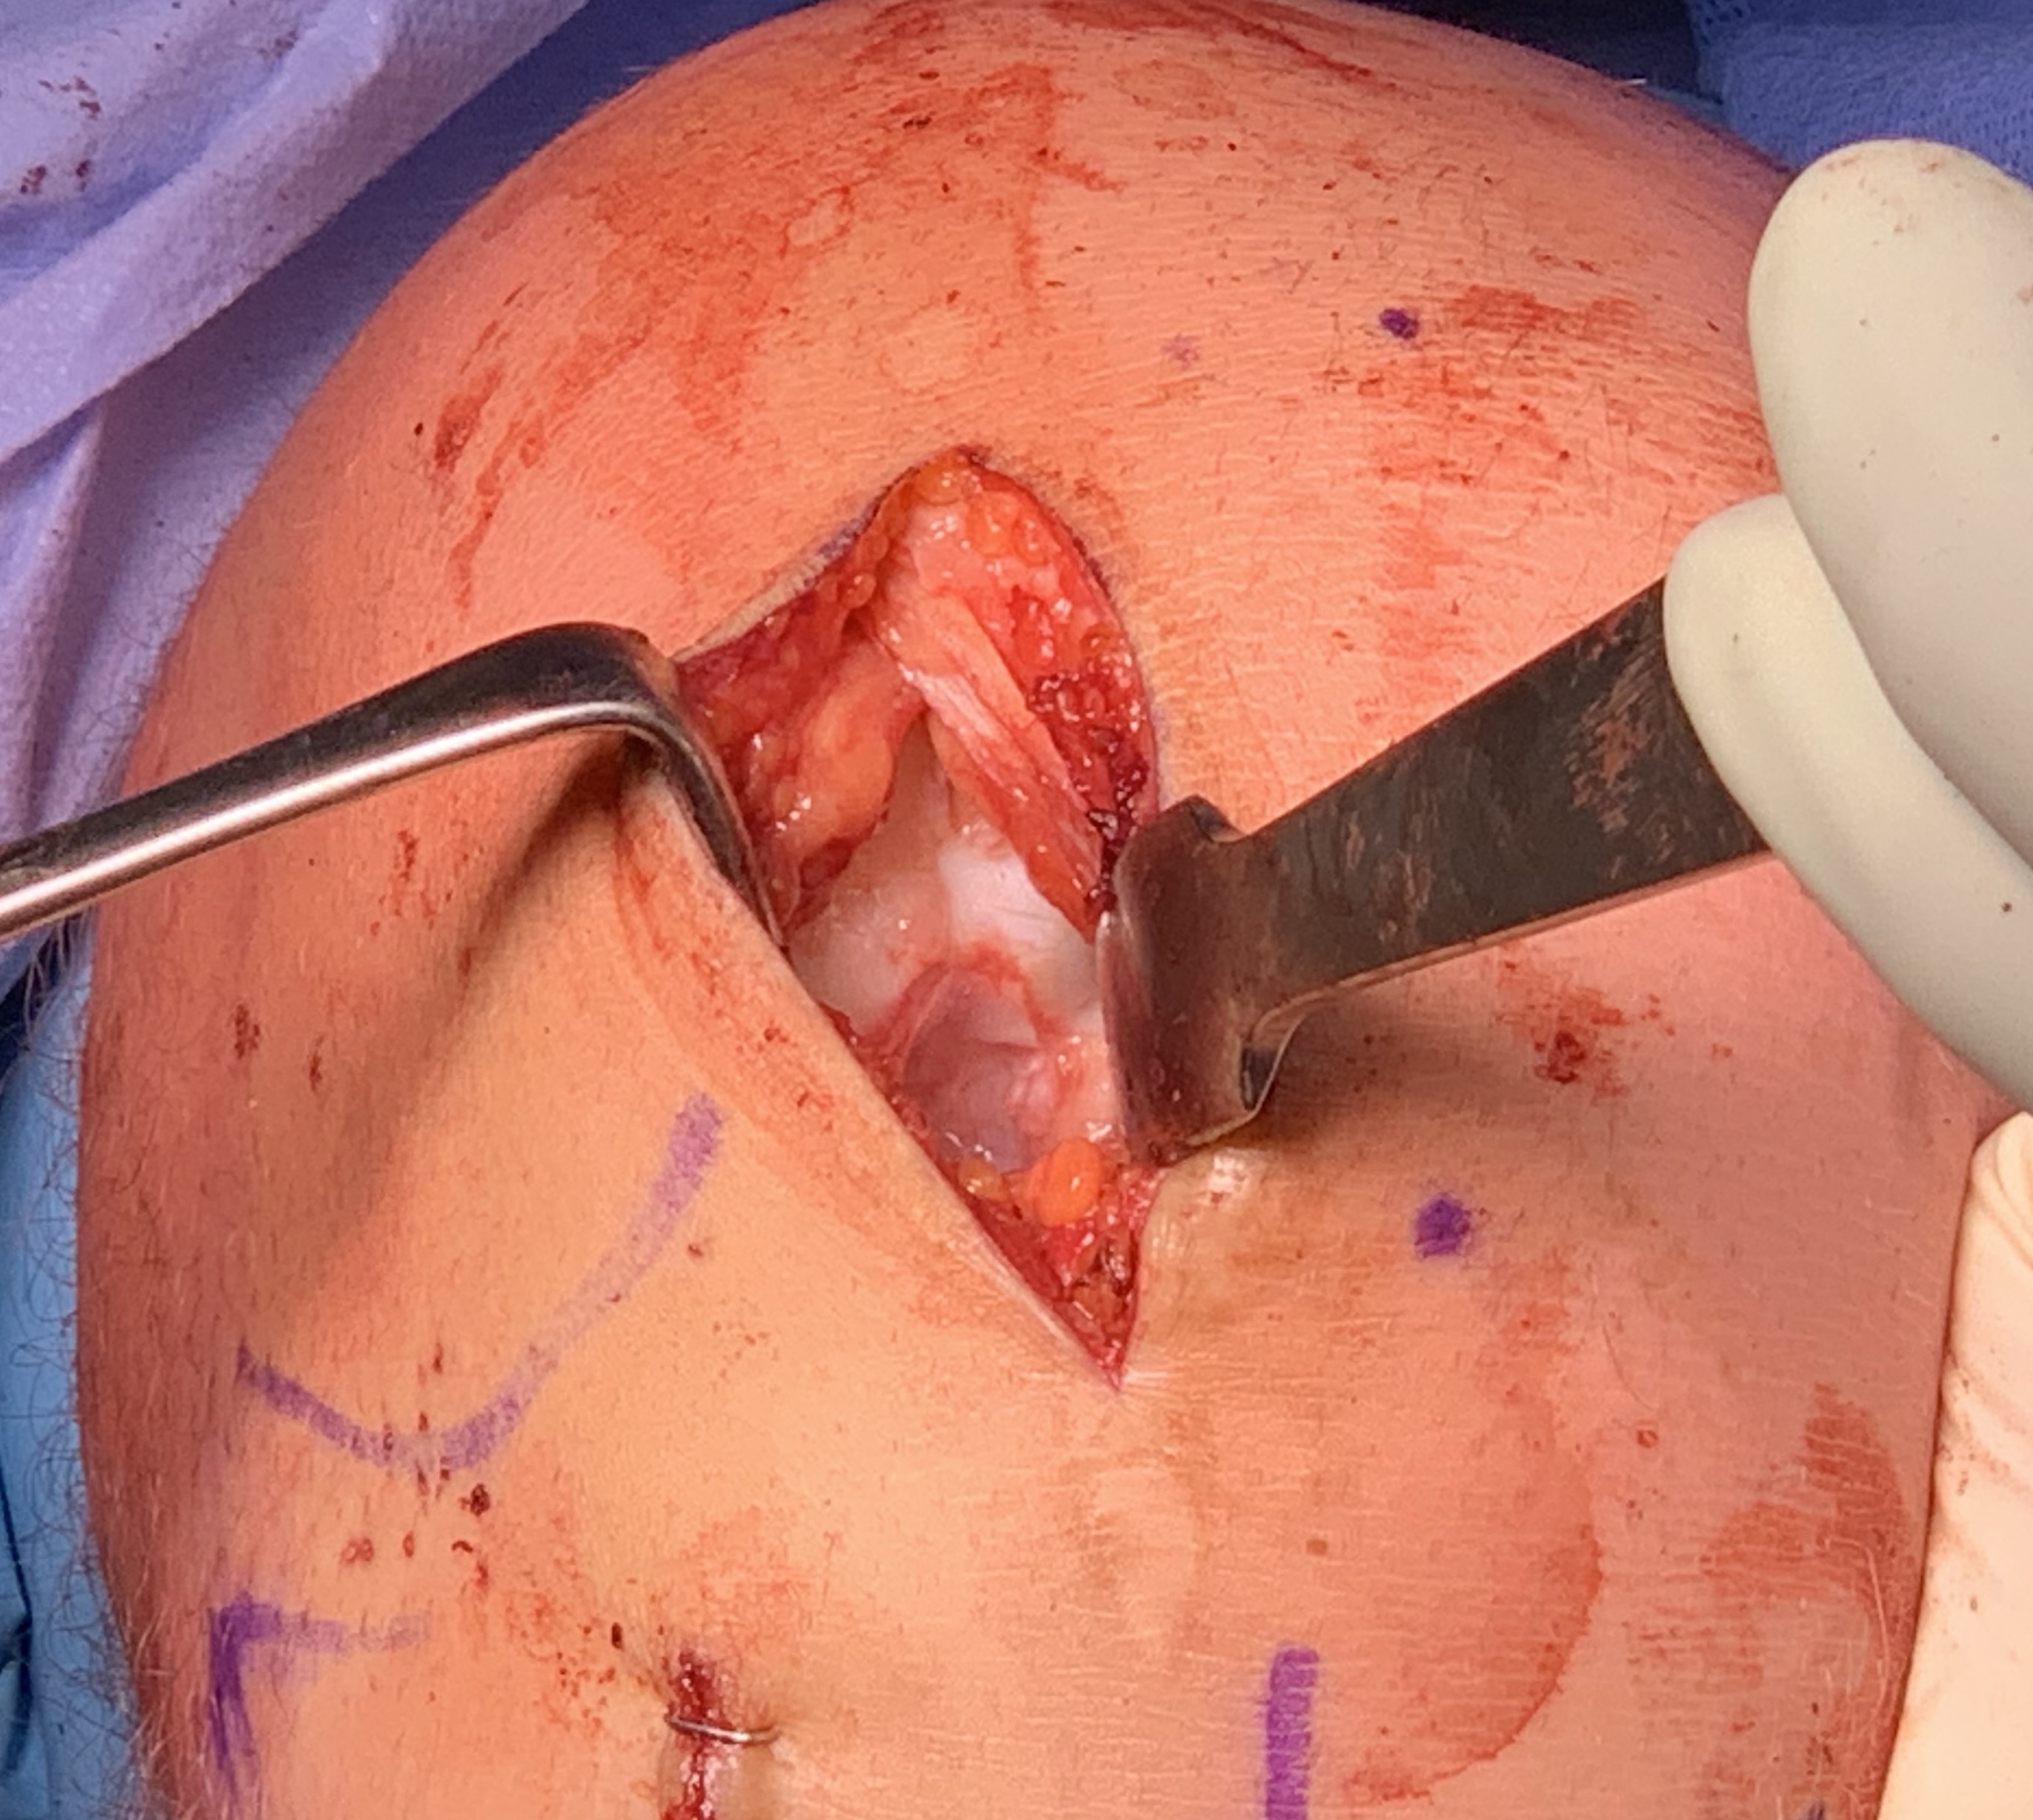

Open bone graft and screw fixation

MFC unstable OCD

LFC unstable OCD